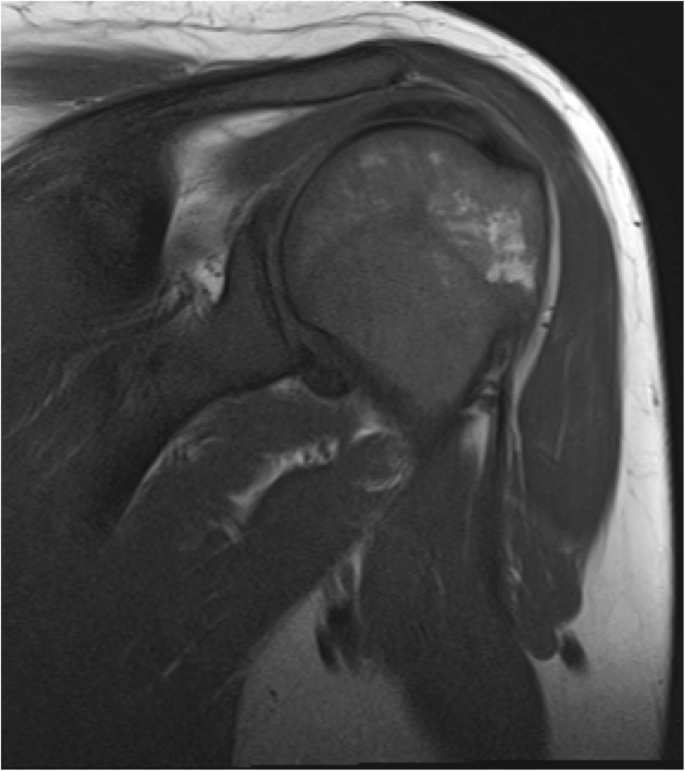

Given these limitations, assessment of acute osseous complications is best performed with initial radiographs followed by prompt MRI assessment [72]. Bone crises may be seen with focal marrow edema on fluid-sensitive sequences [10]. With progressive ischemic insults, osteonecrosis can develop and is evident as T1-weighted hypointense signal with heterogeneous T2-weighted hyperintense signal often with a “double line” of low and high signal reflecting bone infarction [67]. This focal bone involvement can progress further with collapse of the femoral heads and vertebral bodies encountered in severe marrow disease [10]. Other associated complications can be seen including cortical disruption and subperiosteal hemorrhage (Fig. 10) in the setting of massive medullary expansion and cortical thinning, which may also mimic osteomyelitis [116, 117].

Bone infarct and subperiosteal hemorrhage mimicking osteomyelitis in Gaucher disease. A 13-year-old male presented with atraumatic knee pain and swelling. Initial lateral knee radiograph (a) showed subtle periosteal reaction along the posterior metadiaphysis of the distal femur and ill-defined intramedullary sclerosis within the femoral shaft. Follow-up MRI demonstrated intramedullary marrow edema and focal subperiosteal fluid with surrounding inflammatory changes in the popliteal fossa thought to be related to subperiosteal hemorrhage on axial T2-weighted image (b). Coronal post-contrast T1 fat-saturated image (c) demonstrated peripheral serpentine enhancement of areas of bone infarction within the distal femur. The patient was subsequently diagnosed with Gaucher disease after initial workup for hematopoietic malignancy